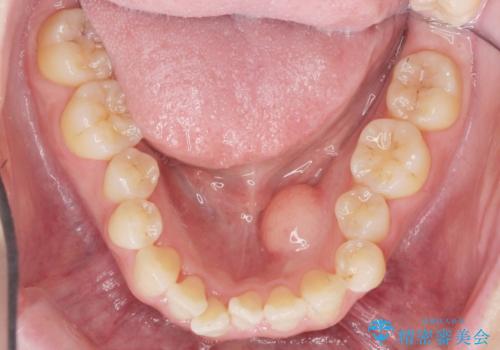

矯正の後戻りを防ぐ骨隆起の切除

- 矯正治療に先立ち、舌の収まりを改善し矯正治療後の後戻りリスクを下げるため、大きな下顎隆起の切除を計画します。

このあと、両側の隆起を除去し、舌の収まりが楽になったと喜んでいただくことができました。